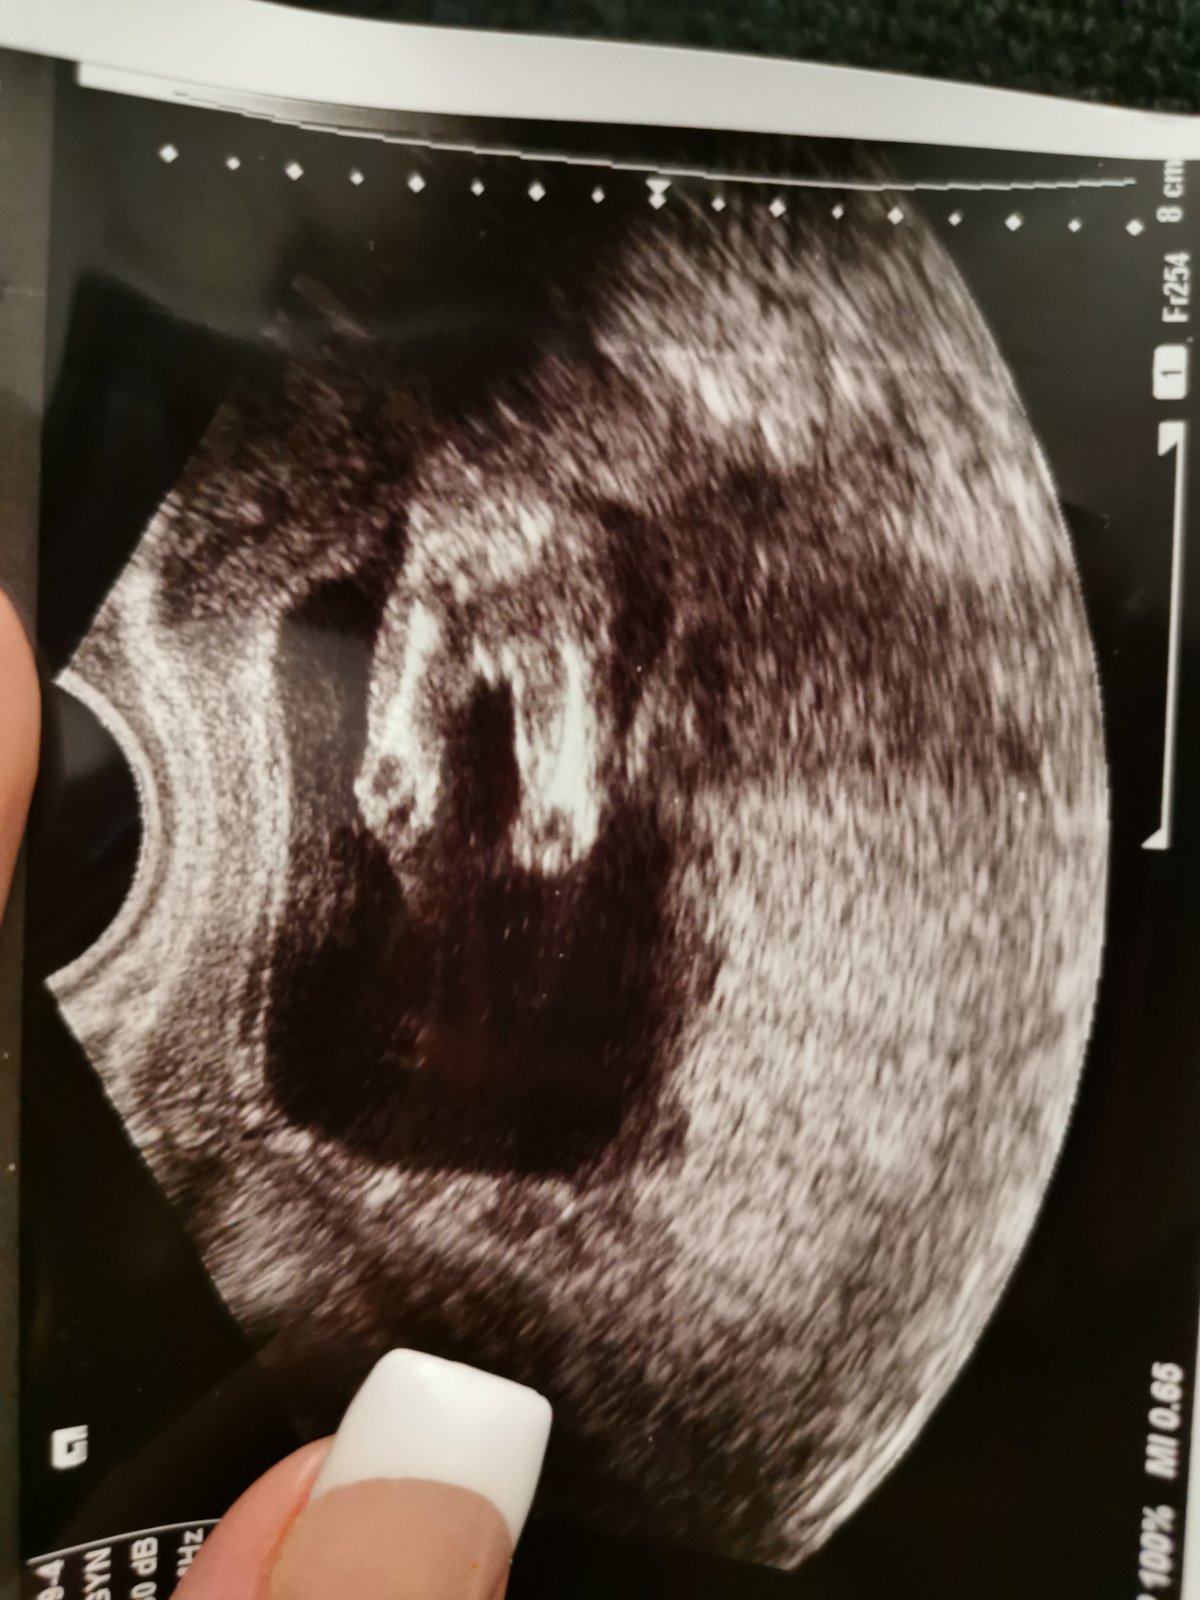

Ahojte, mam otazocku co si myslite ze je na ultrazvuku? V 12 tt mi urcila pohlavie ze to je jednoznacne chlapcek prikladam aj fotku z uktrazvuku z toho tyzdna. A uz 2x co som mala poradnu bolo babo zle otocene a nepotvrdila pohlavie. Dokonca dnes bol naznak ze by teoreticky mohla vidiet pipik lebo sa stveral ako keby do hora zo zadu ale nevidela nic 🤷‍♀️

Dakujem 🍀

@michelleryan chlapec. Mám takú istú fotku

Chlapec😍